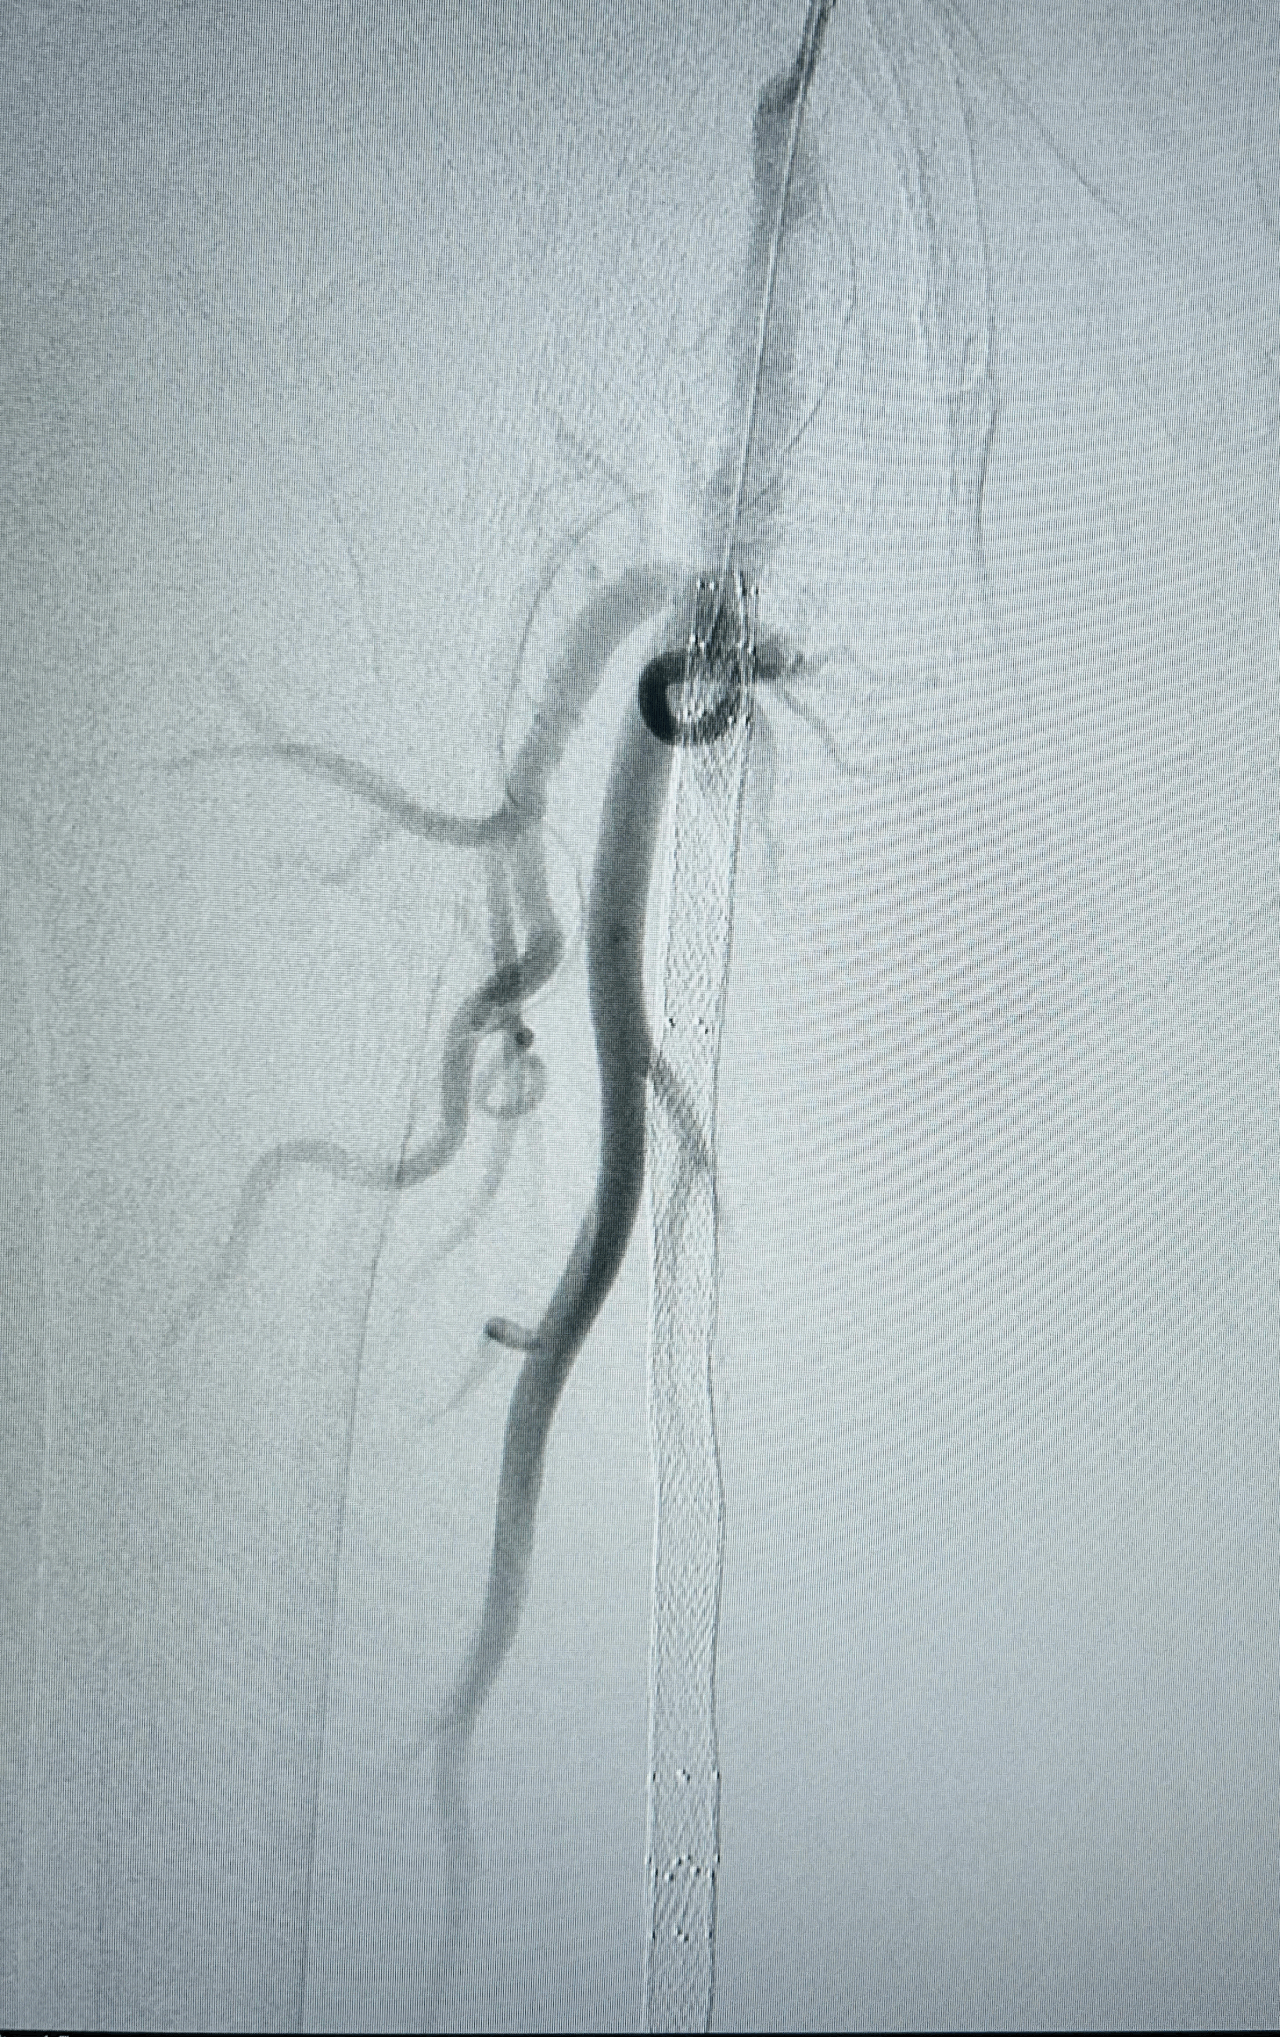

Imagerie pré-opératoire

Angiographie TDM montrant une lésion ectasique de l'artère poplitée rétro-articulaire de 11mm de diamètre, associée à du thrombus circonférentiel entraînant un effet de sténose à plus de 70%, sans calcification.

Altération majeure du lit d'aval artériel : occlusion de la terminaison de l'artère poplitée basse et du tronc tibio-fibulaire, associés à une occlusion proximale des 3 artères de jambe réinjectées à leur tiers proximal par la collatéralité des artères jumelles.

Résultat

Excellent résultat persistant de la recanalisation endoluminale des artères jambières sur le contrôle per-opératoire 15 min après la fin de la recanalisation.

Aucune embolisation distale constatée au niveau des artères du pied.

Disparition de l'ischémie du pied gauche.

Excellent pouls tibial postérieur gauche.